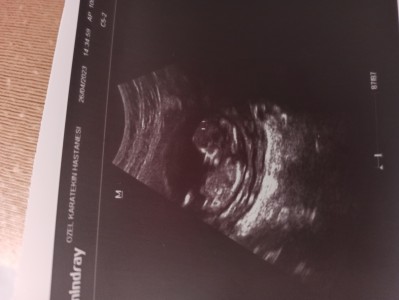

Bugün ikili tarama için muayene oldum yarına gün verdi sizinde tahminlerinizi almak istedim kızçeler

Görür görmez kız diyesim geldi

Erkek bence hayırlısı olsun inşallah eli ayağa düzgün sağlıklı olsun inşallah

Kiz gibi geldi